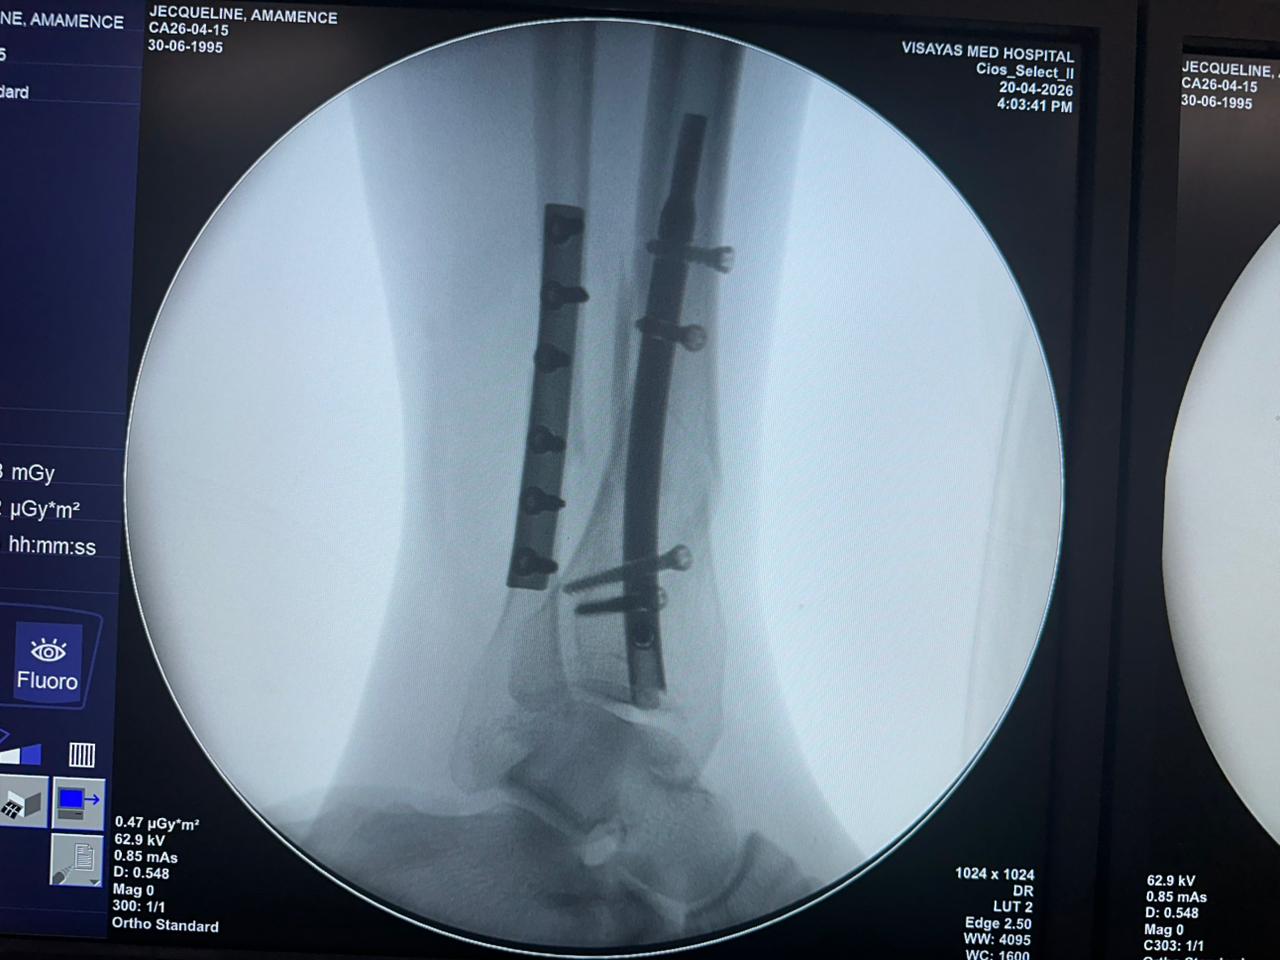

Caso di studio sulla fissazione del chiodo tibiale distale con supporto per placca peroneale

Fluoroscopia intraoperatoria con arco a C, viste AP e laterali

Questo caso prevedeva la fissazione tibiale distale utilizzando un chiodo tibiale distale intramidollare. La fluoroscopia intraoperatoria ha confermato la posizione del chiodo, delle viti di bloccaggio distali e della fissazione della placca peroneale.